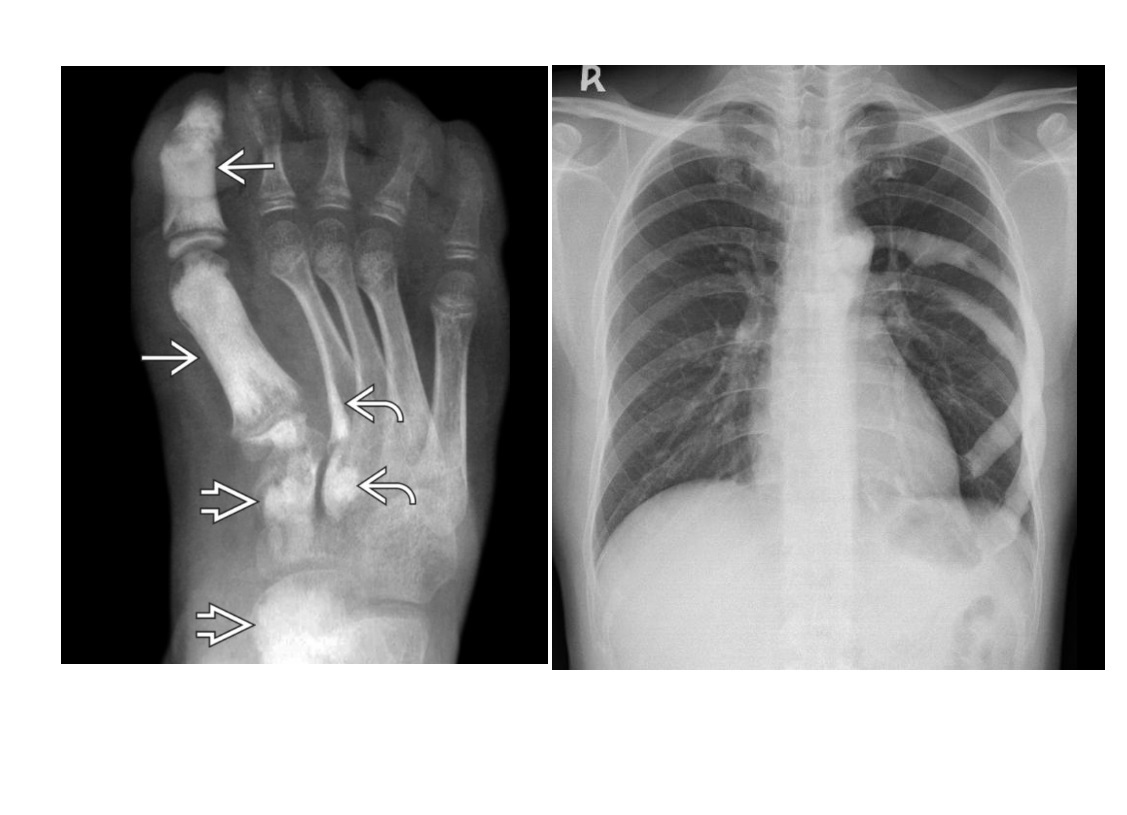

ENCHONDROMA

Commonest location Hands/feet

Long bones: proximal humerus > distal and proximal femur > proximal tibia

Intramedullary and metaphysis

multiple enchondroma

Maffuci - haemangioma

Olliers - multiple enchondroma only

DDx

-Brown tumor (hyperparathyroidism),

-sarcoid - lace like bone lesion phalanges

-intraosseous ganglion

-metastatic disease.

Chondrosarcoma

May be cecondary to

- Osteochondromas

- enchondromas

Chondrosarcomas occur in the pelvis, femur, humerus.